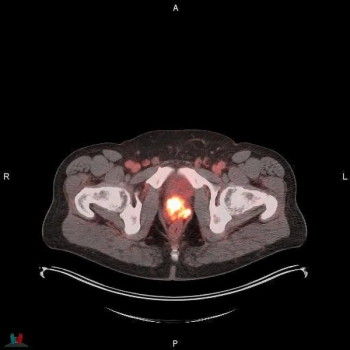

Sixty-five percent of patients with newly diagnosed high-risk prostate cancer may have extraprostatic extension on MRI, and PSMA PET/CT findings suggest those with Gleason scores of eight or higher have more than double the risk of metastasis, according to a new study presented at the European Congress of Radiology (ECR).